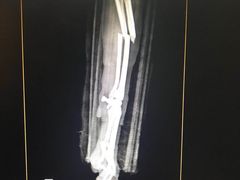

• 北京赛佳动物医院

• -北京赛佳动物医院